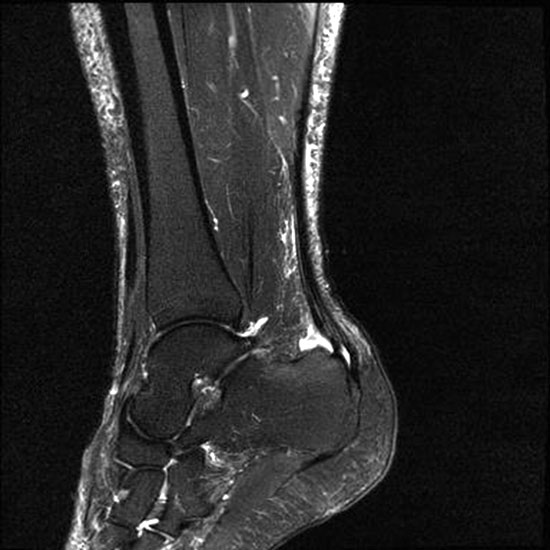

Hier befindet sich ca. 3-5 cm proximal des Tuber calcanei ein als „kritische Zone“ benannter Bezirk, der durch eine ungünstige arterielle Blutzufuhr gekennzeichnet ist (letzte Wiese). Hier finden sich häufig spindelförmige Schwellungen, die bei MRT-Diagnostik nicht selten partielle Nekrosen und Partialrupturen der Achillessehne aufweisen (Abb. 14).

Die sonographische Diagnostik eignet sich primär zur Erkennung schmerzhafter Prozesse im Verlauf der Achillessehne und kann bei Bedarf durch Röntgen bzw. MRT ergänzt werden. Besonders bei längeren Verläufen und kräftigen spindelförmigen Schwellungen (>9mm, Normwert <5mm) im Bereich der kritischen Zone sollte ein MRT zum Ausschluss von Nekrosezonen und Partialrupturen vor Therapiebeginn veranlasst werden. Die sonographisch leicht zu erfassende Veränderung der Sehnendicke im mittleren Sehnenanteil ist ein guter Indikator für die Schwere der Erkrankung und die Beurteilung des Behandlungsverlaufes. Die sichtbaren Veränderungen am distalen knöchernen Ansatz der Sehne sind diskreter.

Insbesondere bei größeren Partialrupturen (Abb. 14) sollten operative Verfahren erörtert werden. Kleinere Partialrupturen sind der ESWT gut zugänglich, wie die beiden nachfolgenden Beispiele zeigen:

In Abhängigkeit des Befundes kann die Verwendung eines Vacoped-Stiefels für die Zeit der Therapie sinnvoll sein. Eine MRT-Kontrolle nach Therapie einer Partialruptur kann nach 5-6 Monaten durchgeführt werden.